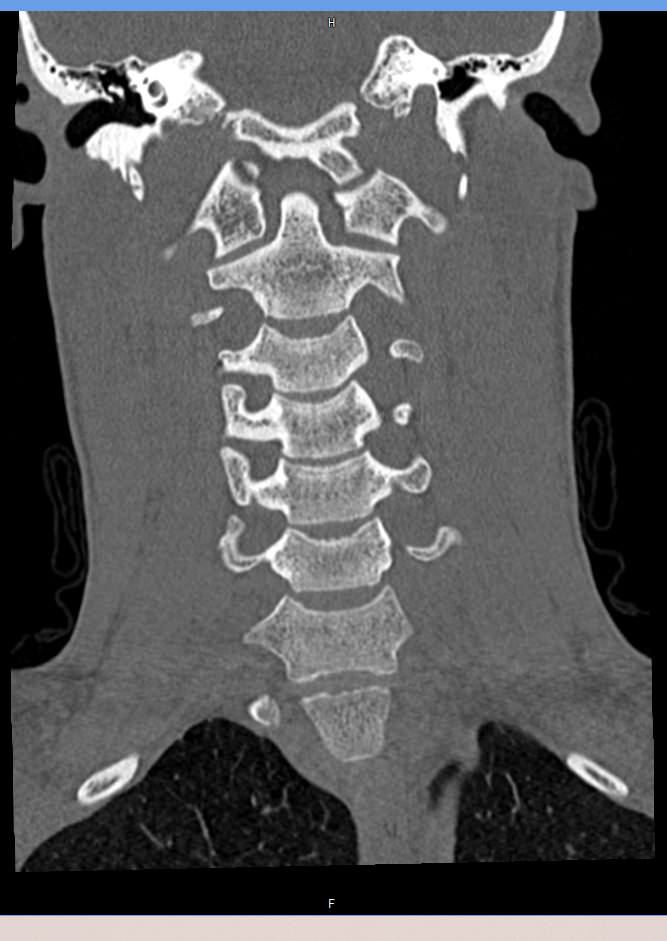

На снимках КТ хорошо визуализируются позвоночные суставы, суставные поверхности, межпозвонковые диски, которые часто подвержены дегенеративно-дистрофическим процессам. На томограммах также можно оценить состояние позвоночного канала, в котором располагается спинной мозг, выявить участки его сужения и предположить степень воздействия на спинномозговые структуры.

При обследовании шейного отдела позвоночника оценивается область основания черепа, семь шейных позвонков, верхние грудные позвонки. Помимо костных структур мультиспиральная КТ показывает состояние близлежащих органов и тканей: трахеи, пищевода, лимфатических узлов, кровеносных сосудов на исследуемом уровне.